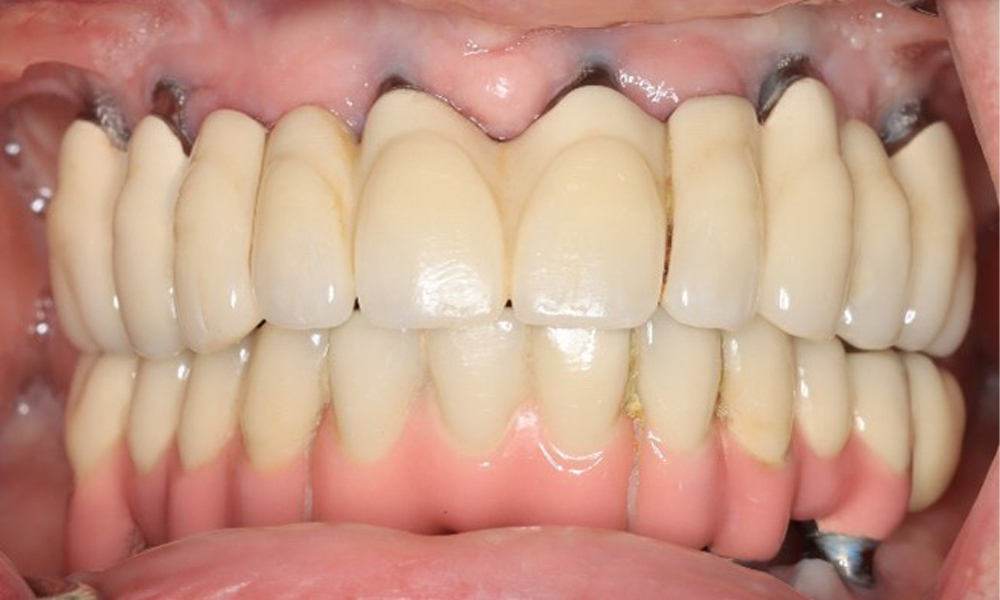

Eine 74-jährige Patientin stellt sich in der Sprechstunde vor. Die Anamnese zeigt, dass die Patientin gut eingestellten Bluthochdruck hat und Lixiana einnimmt. Weiterhin hatte die Patientin im Jahr 2020 ein Nierenkarzinom. Die Lebensgewohnheiten der Patientin sind unauffällig. Die Patientin hat keine eigenen Zähne mehr. Sie hat im Oberkiefer und Unterkiefer jeweils sechs Implantate, die mit Kronen bzw. über Brücken versorgt sind. Anhand der aktuellen Befunde lässt sich keine periimplantäre Mukositis bzw. Periimplantitis feststellen; vereinzelte (geringfügige) Blutungen an den Implantat(-versorgungen) liegen vor.

Frontansicht Gebiss (Ober- und Unterkiefer)

Abb. 3: Frontansicht